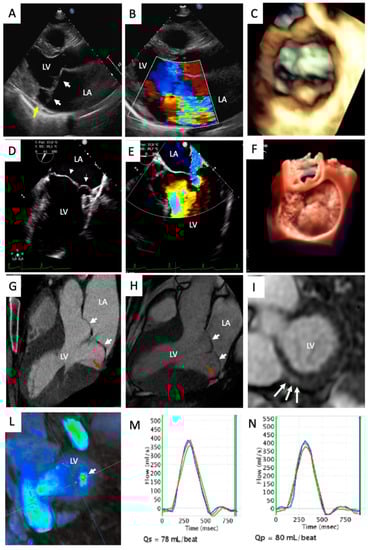

4.2. Mitral Valve Annulus Alterations

4.3. Myocardial Structural Abnormalities

4.4. Myocardial Contraction Abnormalities